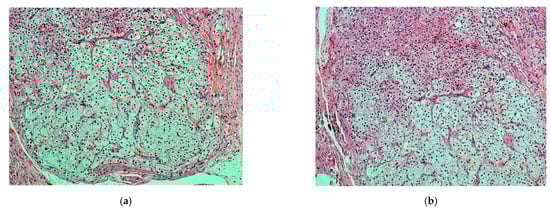

Microscopically with H&E (hematoxylin eosin) staining, many chorionic villi and trophoblastic cell islands were observed between fibrin thrombi and the luminal blood clots in the salpinx (Figure 1a). The endometrial samplings exhibited morphological features of a hypersecretory or gestational endometrium, obviously caused by increased progesterone effect, confirming the initial clinical diagnosis of ectopic tubal pregnancy. Meanwhile, the very small nodule discovered was located between bundles of smooth muscle cells of the outer longitudinal muscularis layer, with interspersed loose connective tissue of serosa present. The nodule appeared well demarcated, it was surrounded by a thin fibrous rim and was composed of two intermingled but distinct cell populations, arranged in small parallel cords and trabeculae (Figure 1b).

Figure 1. Fallopian tube: (a) fibrotic chorionic villi and trophoblast in the lumen of the salpinx (H & E, ×40); (b) demarcated nodule in the fallopian fibromuscular layer (blue arrow) (H & E, ×20).